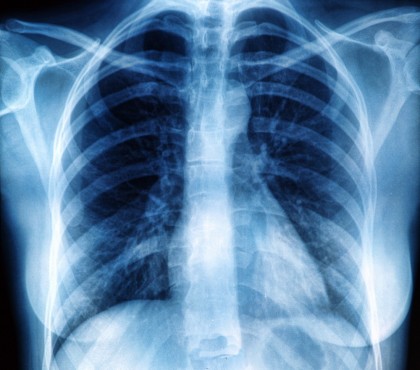

Sindromul, care se manifestă prin simptome reumatologice precum erupții cutanate, artrită și dureri musculare, a fost identificat în principal la pacienți caucazieni, diferind astfel de distribuția tipică a DM observată mai frecvent în rândul asiaticilor.

Echipa a utilizat BoNE, un cadru computațional dezvoltat la UC San Diego, pentru a analiza datele și a descoperit că pacienții cu niveluri ridicate de MDA5 corespund cu niveluri înalte de interleukină-15, un citokin implicat în inducerea fibrozei pulmonare.